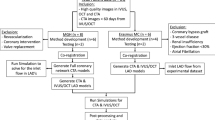

Characterization of endothelial shear stress (ESS) may allow for prediction of the progression of atherosclerosis. The aim of this investigation was to develop a non-invasive approach for in vivo assessment of ESS by coronary computed tomography angiography (CTA) and to compare it with ESS derived from invasive coronary angiography (ICA). A total of 41 patients with mild or intermediate coronary stenoses who underwent both CTA and ICA were included in the analysis. Two geometrical models of the interrogated vessels were reconstructed separately from CTA and ICA images. Subsequently, computational fluid dynamics were applied to calculate the ESS, from which ESSCTA and ESSICA were derived, respectively. Comparisons between ESSCTA and ESSICA were performed on 163 segments of 57 vessels in the CTA and ICA models. ESSCTA and ESSICA were similar: mean ESS: 4.97 (4.37–5.57) Pascal versus 4.86 (4.27–5.44) Pascal, p = 0.58; minimal ESS: 0.86 (0.67–1.05) Pascal versus 0.79 (0.63–0.95) Pascal, p = 0.37; and maximal ESS: 14.50 (12.62–16.38) Pascal versus 13.76 (11.44–16.08) Pascal, p = 0.44. Good correlations between the ESSCTA and the ESSICA were observed for the mean (r = 0.75, p < 0.001), minimal (r = 0.61, p < 0.001), and maximal (r = 0.62, p < 0.001) ESS values. In conclusion, geometrical reconstruction by CTA yields similar results to ICA in terms of segment-based ESS calculation in patients with low and intermediate stenoses. Thus, it has the potential of allowing combined local hemodynamic and plaque morphologic information for risk stratification in patients with coronary artery disease.